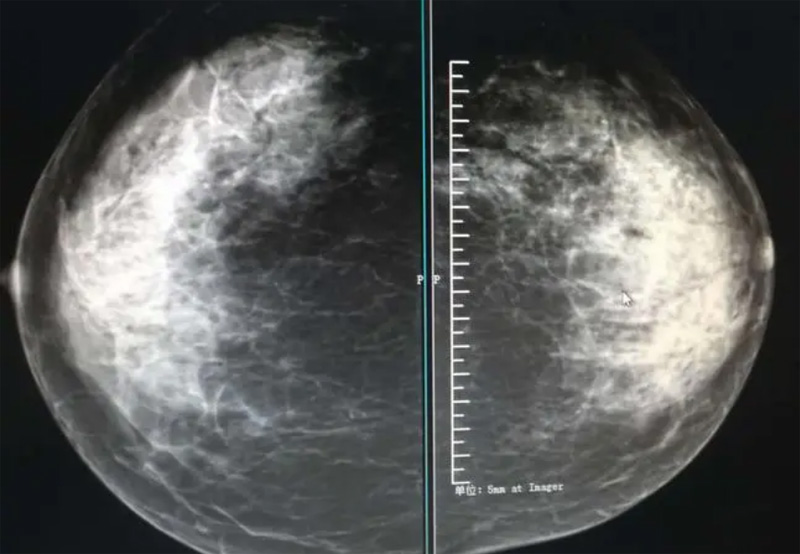

攝影診斷規(guī)范乳腺DR有頭尾位及內(nèi)外側(cè)斜位診斷概念和診斷術(shù)語

乳腺DR的檢查中為了讓乳腺相關(guān)疾病的篩查需要更高質(zhì)量的檢查圖像。檢查前期的準(zhǔn)備工作非常重要。醫(yī)生跟病患的有效溝通。要跟檢查者說明檢查過程,特別是體位跟擠壓乳房帶來的不適應(yīng)。放松心情,檢查過程中得到充分的合作。正確的擺正位置乳腺DR可以拍攝到更優(yōu)質(zhì)清洗高質(zhì)量的X線圖像。乳腺DR檢查需要再月經(jīng)后檢查,但是對病癥明顯的就不受這個限制。

乳腺DR攝影體位有頭尾位及內(nèi)外側(cè)斜位,

乳房在片子的中央,乳頭切線位,可見小部分胸大肌,內(nèi)側(cè)乳腺組織應(yīng)全部包括在片中,外側(cè)乳腺組織盡可能包括在片中。一張好的MLO位圖像顯示如下:乳房被推向前上,乳腺實質(zhì)充分展開,胸大肌可見,較松弛,下緣達到乳頭水平,乳頭在切線位,部分腹壁包括在片中,但與下部乳腺分開,絕大部分乳腺實質(zhì)顯示在片中。乳腺組織外緣可見乳頭的輪廓;乳腺后方的脂肪組織被很好地顯示出來,乳房無皺褶。對于CC位及MLO位顯示不良或未包全的乳腺實質(zhì),可以根據(jù)病灶位置的不同選擇以下體位:外內(nèi)側(cè)位(LM)、內(nèi)外側(cè)位(ML)、內(nèi)側(cè)頭尾軸位(MCC)、外側(cè)頭尾軸位(LCC),尾葉位(CLEO)及乳溝位。在臨床實踐中,對于常規(guī)體位上發(fā)現(xiàn)的異常改變,可以進一步采取一些特殊的攝影技術(shù),包括局部加壓攝影、放大攝影或局部加壓放大攝影技術(shù)。

3、乳腺實質(zhì)背景的確定:觀察乳腺實質(zhì)與脂肪的構(gòu)成比例,了解乳腺實質(zhì)類型,以判斷對某些乳腺攝影征象敏感性的影響,有利于確定乳腺攝影對疾病的診斷價值。

必須指出的是,美國放射學(xué)會提出的乳腺影像報告和數(shù)據(jù)系統(tǒng)(Breast Imaging Reporting and Data System, BI-RADS)將乳腺分為4型:脂肪型(乳腺內(nèi)幾乎全部為脂肪組織,腺體組織占25%以下)、少量腺體型(乳腺內(nèi)散在腺體組織,大約占25%~50%)、多量腺體型(乳腺呈不均勻致密表現(xiàn),腺體組織大約占51%~75%)、致密型(乳腺組織非常致密,腺體組織占75%以上)。這種分型的主要意義在于說明X線對不同乳腺類型中病變檢出的敏感性不同,對發(fā)生在脂肪型乳腺中病變的檢出率很高,而對發(fā)生在致密型乳腺中病變的檢出率則有所降低,臨床醫(yī)師了解這一點很重要。